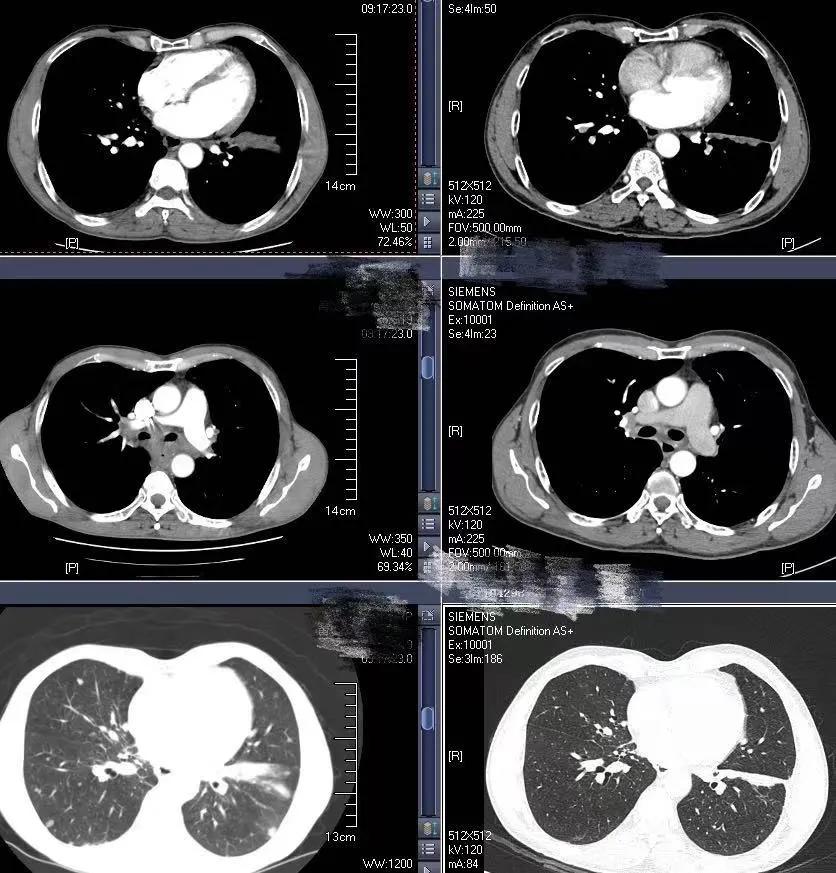

2020-6-19患者行全身PET/CT示:

1、左下肺前内基底段支气管开口处结节,糖代谢增高,考虑中央型肺癌并远端阻塞性炎症、不张;全身(双侧颈部、双侧锁骨上下窝、两侧肺门、纵隔、贲门旁、胰头后方、腹主动脉旁及双侧髂血管旁)多发淋巴结转移;双肺多发转移;肝S4及S5转移;胰头部结节转移;全身多发骨转移;综上,建议活检除外结核。

2、甲状腺双侧叶多发结节,糖代谢增高,不除外恶性肿瘤,建议追踪。左侧肾上腺稍增粗,糖代谢轻度增高,建议追踪。